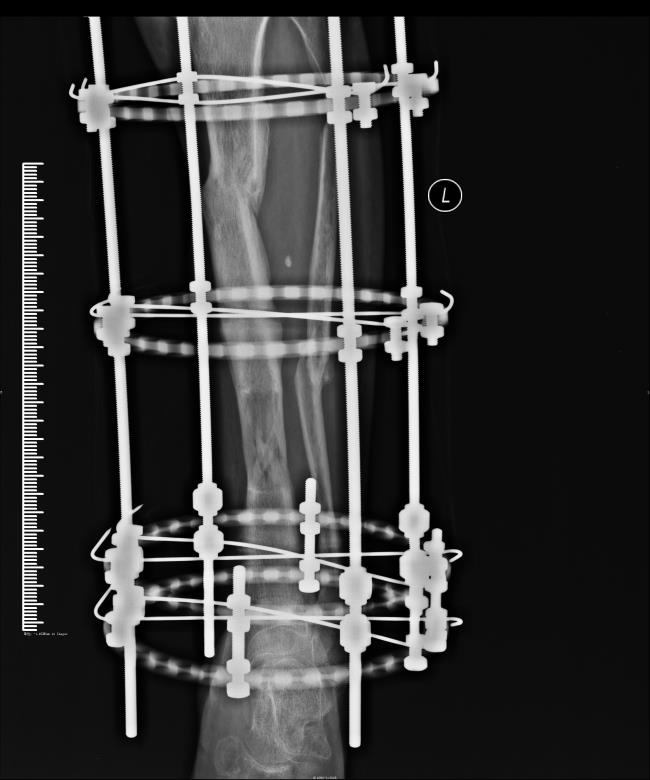

医药联合外固架肢体延长技术